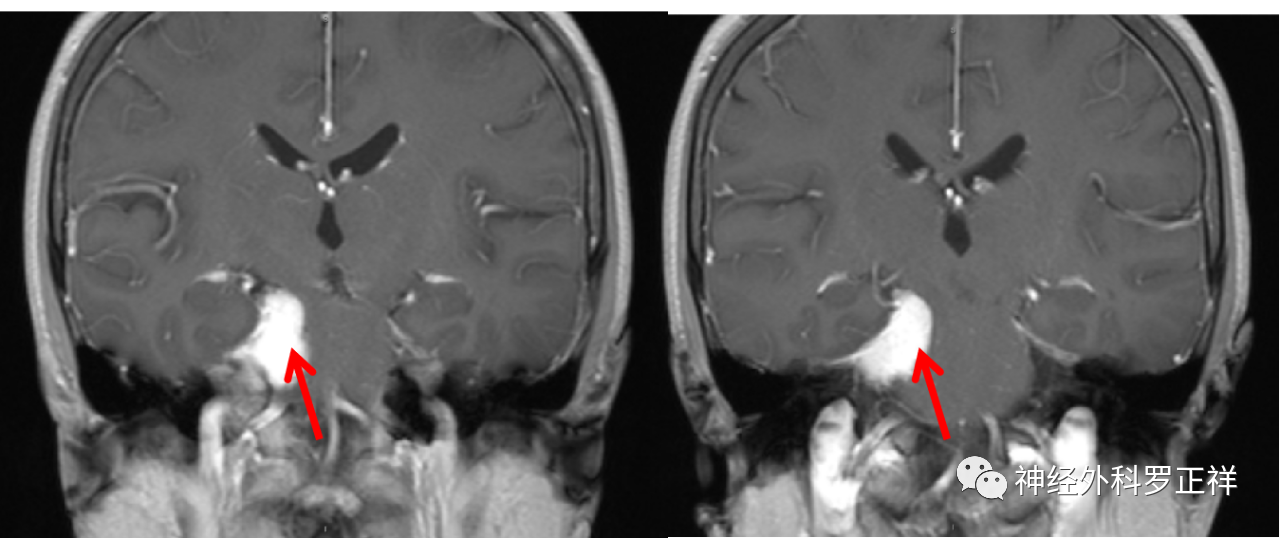

(见下图,上三张为术前,下三张为同一层面术后复查对比,提示肿瘤全切除)

患者48岁女性,以“右侧面部疼痛”为主诉入院。

门诊诊断为三叉神经痛。进了病房后,给予做磁共振检查显示为岩斜区肿瘤。

术前磁共振MRI增强显示中颅窝岩骨尖部和后颅窝(小脑幕下、斜坡)病变,术后1天磁共振复查显示肿瘤全切,无残留,术后患者恢复良好,没有不良症状发生。通过颞下经小脑幕入路一次手术全切病变,避免分期二次手术的痛苦。